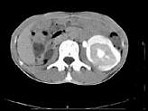

- 多项选择题女,32岁, 左腰部胀痛不适1年余,10年前因右输尿管结石、右肾重度积水行右肾切除术, CT检查如图所示,下列说法正确的是 ( )

A、平扫左肾周可见不规则的环形低密度影

B、增强扫描,肾皮质明显强化而周围的低密度影无强化

C、增强扫描肾实质期,肾实质强化而周围的低密度影无强化

D、增强扫描延迟期,肾实质强化减退而其周围则呈高密度影,对比明显

E、考虑为左侧尿外渗